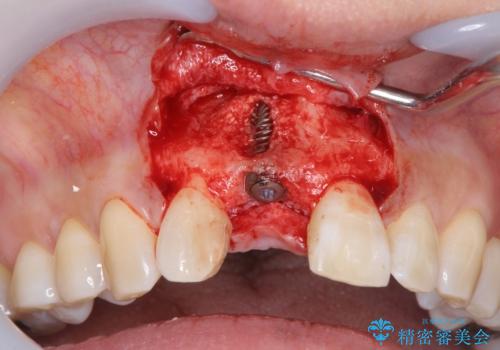

審美的・機能的に良好な位置に埋入するには、骨量が十分ではなかったため骨の造成を併用したインプラント埋入外科手術を行います。

前歯のインプラントを審美的に仕上げるには、インプラント周囲に十分な骨の量と厚みのある歯肉、そして埋入位置の精密な位置付けが重要です。